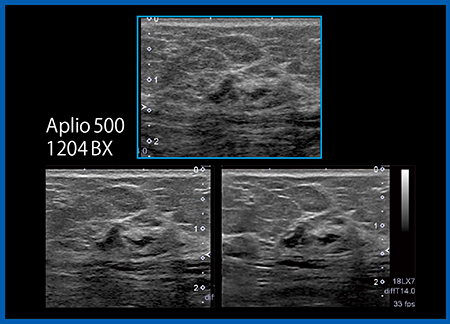

超広帯域高周波リニアプローブ「PLI-1205BX」(5〜18MHz)は,1本で低周波から高周波まで幅広くカバーし,深部の描出と高分解能を併せ持つことが特長である。従来のプローブと比べ,乳房では体表に近いクーパー靭帯から深部の筋膜や大胸筋のラインまで,高い分解能を保って描出することができる(図1)。従来プローブでは辺縁がぼやけて脂肪と見分けが付きにくかった深部の粘液癌などの構造物が,より明瞭に描出できることが期待される。

図1 超広帯域高周波リニアプローブPLI-1205BX(左)と従来プローブ(右)の画像比較